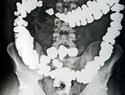

tiêu hoá, làm tiêu hoá (thức ăn)